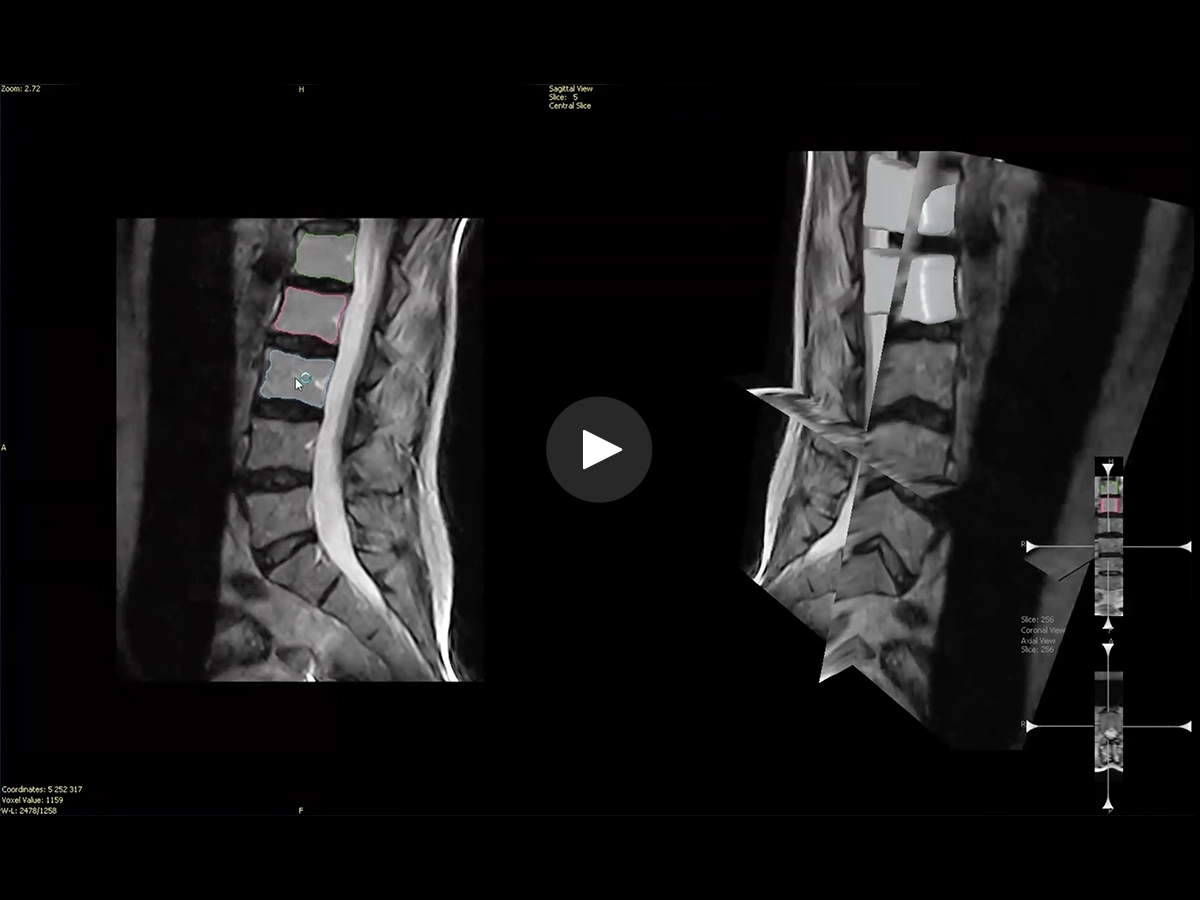

Q-Spine is a support tool for the Visualization and Quantification of relative biomechanical modifications comparing Weight-Bearing and supine MRI spine examinations using Fast Spin Echo T2 acquisitions.

• Facilitates and simplifies the analysis of WB versus recumbent MRI by semiautomatic segmentation of the Lumbar-spine.

• Gives a numerical quantification of the relative changes.

• Reliable and coherent measurements by taking out the “human factor”.

• Enhance patient follow-up with numerical evidence.

• Improved confidence in surgery planning and diagnosis of the spine.

• Vertebral wedging

• Intervertebral Translation

• Spinal canal section

• Foramen area

• Intervertebral Angles

• Spine curvature

• Spinal canal thickness

• Listhesis Index

• Vertebral collapse